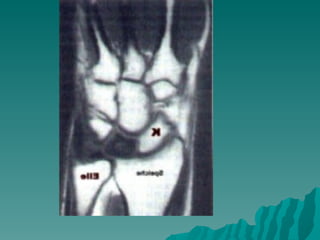

Keinböck hastalığı

 Genellikle

yetişkinlerde ve

unilateral

 El bileğinde ağrı ve

hassasiyet

r          Travmalar ve

tekrarlayan

mikrotravmalar

Rober Kienböck (1871 -1953)     suçlanır.

 X-Ray: lunat kemikte

yaygın opasite

kemikte yassılaşma,

fregmantasyon